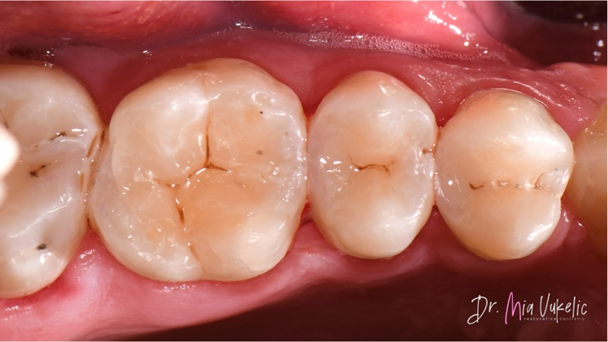

Na het polijsten kreeg de vulling een verzegeling (PermaSeal™-composietsealer, Ultradent Products). Tot slot werd de occlusie gecontroleerd en werden röntgenopnamen gemaakt.

Zoals te zien is op de foto’s van het eindresultaat, zorgt Transcend-composiet voor een zeer esthetische restauratie. Het sectionele matrixsysteem Halo leverde een uitstekende approximale anatomie, wat bleek uit de röntgenopname.